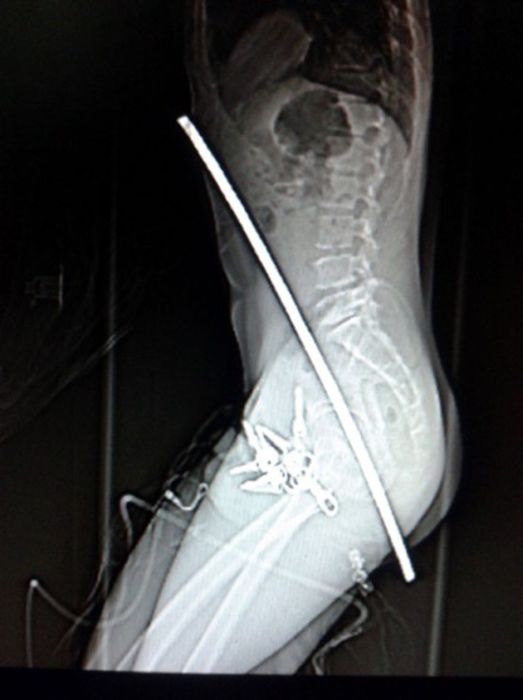

Жуткие рентгеновские снимки

Порой даже не верится, с какими странными и необычными повреждениями в травматологию могут поступить пострадавшие. Всю эпичность профессии врачей травматологии могут с легкостью подтвердить рентгеновские снимки. Просто жесть, да и только..